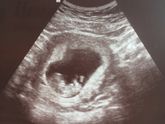

У кого так было срок 35-36 недель хожу и в промежность давить,бывает резями и тонус? Стоит пессарий, ничего не говорят завтра вот на узи шейку хотят посмотреть